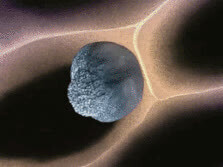

9.白细胞: 当病菌侵入人体体内时,白细胞能通过变形而穿过毛细血管壁,集中到病菌入侵部位。这就像在穿越时空隧道。

1.免疫细胞既能抵抗、消灭入侵人体的病菌,又能清除自身衰残、癌变的细胞。

4.免疫细胞也可穿过血管壁奔赴“战场”,向炎症和创伤组织处进军、围剿。

5.免疫细胞死亡时也会膨胀、爆炸和分裂。